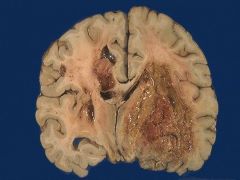

胶质母细胞瘤:肿瘤高度恶性生长快,病程短,自出现症状至就诊多数在3个月之内,高颅内压症状明显,33%患者有癫痫发作,20%患者表现淡漠、痴呆、智力减退等精神症状,(患者)可出现不同程度的偏瘫,偏身感觉障碍、失语和偏盲等。如果您还有治疗上面的疑问可以与我们近一步的沟通,我们会给患者提供最佳的治疗方案和最方便的医疗药物的提供。有问题可以咨询海得康,海外就医咨询机构!